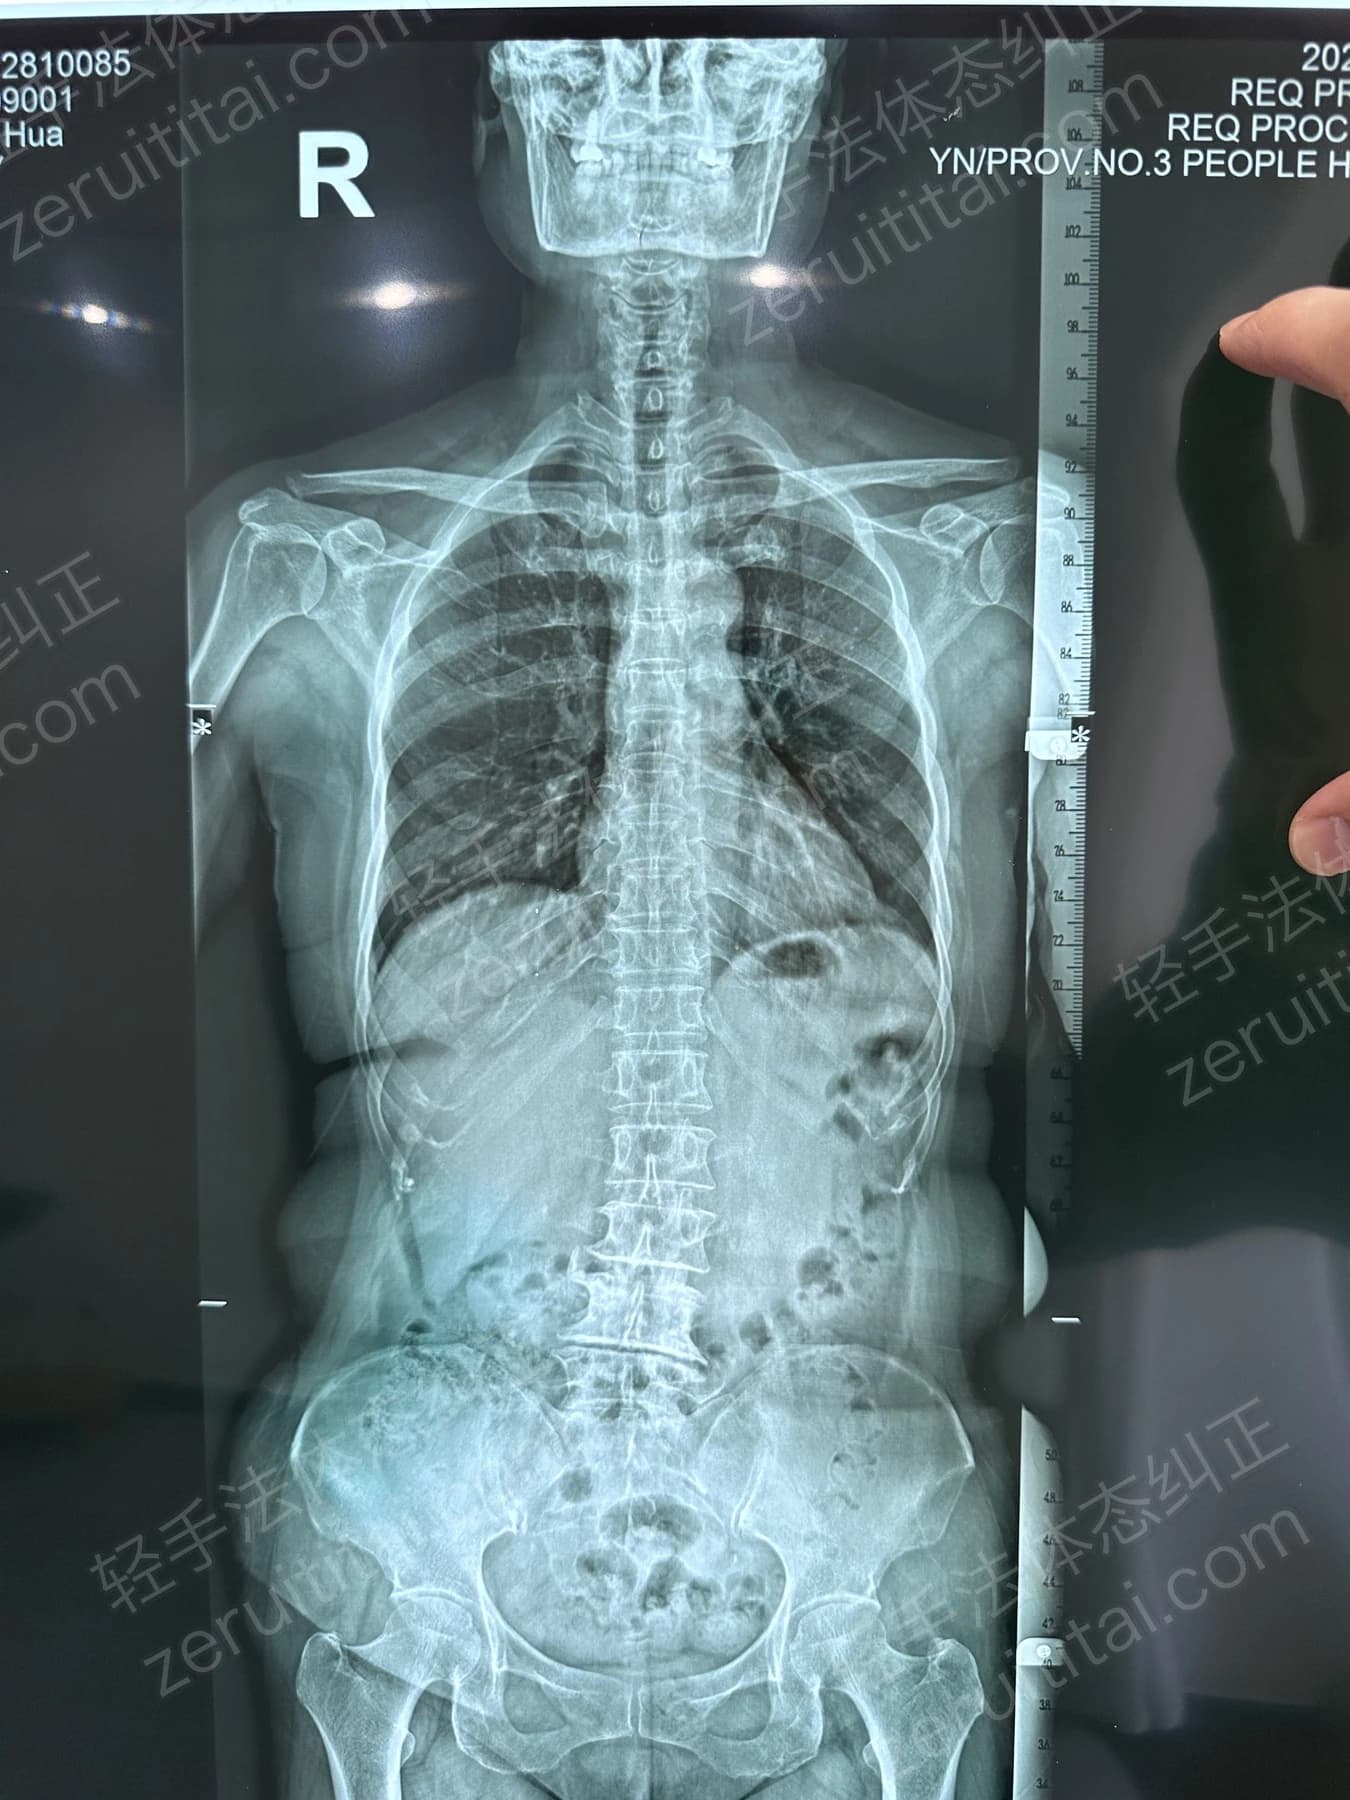

2022.12.26

第 3 次记录